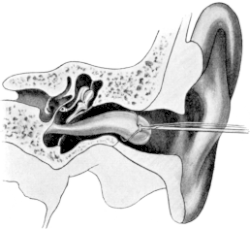

| 209. | Eustachian Catheter | 365 |

| 210. | Passing the Eustachian Catheter | 365 |

| 211. | Passing the Eustachian Catheter | 365 |

| 212. | Passing the Eustachian Catheter | 366 |

| 213. | Passing the Eustachian Catheter | 366 |